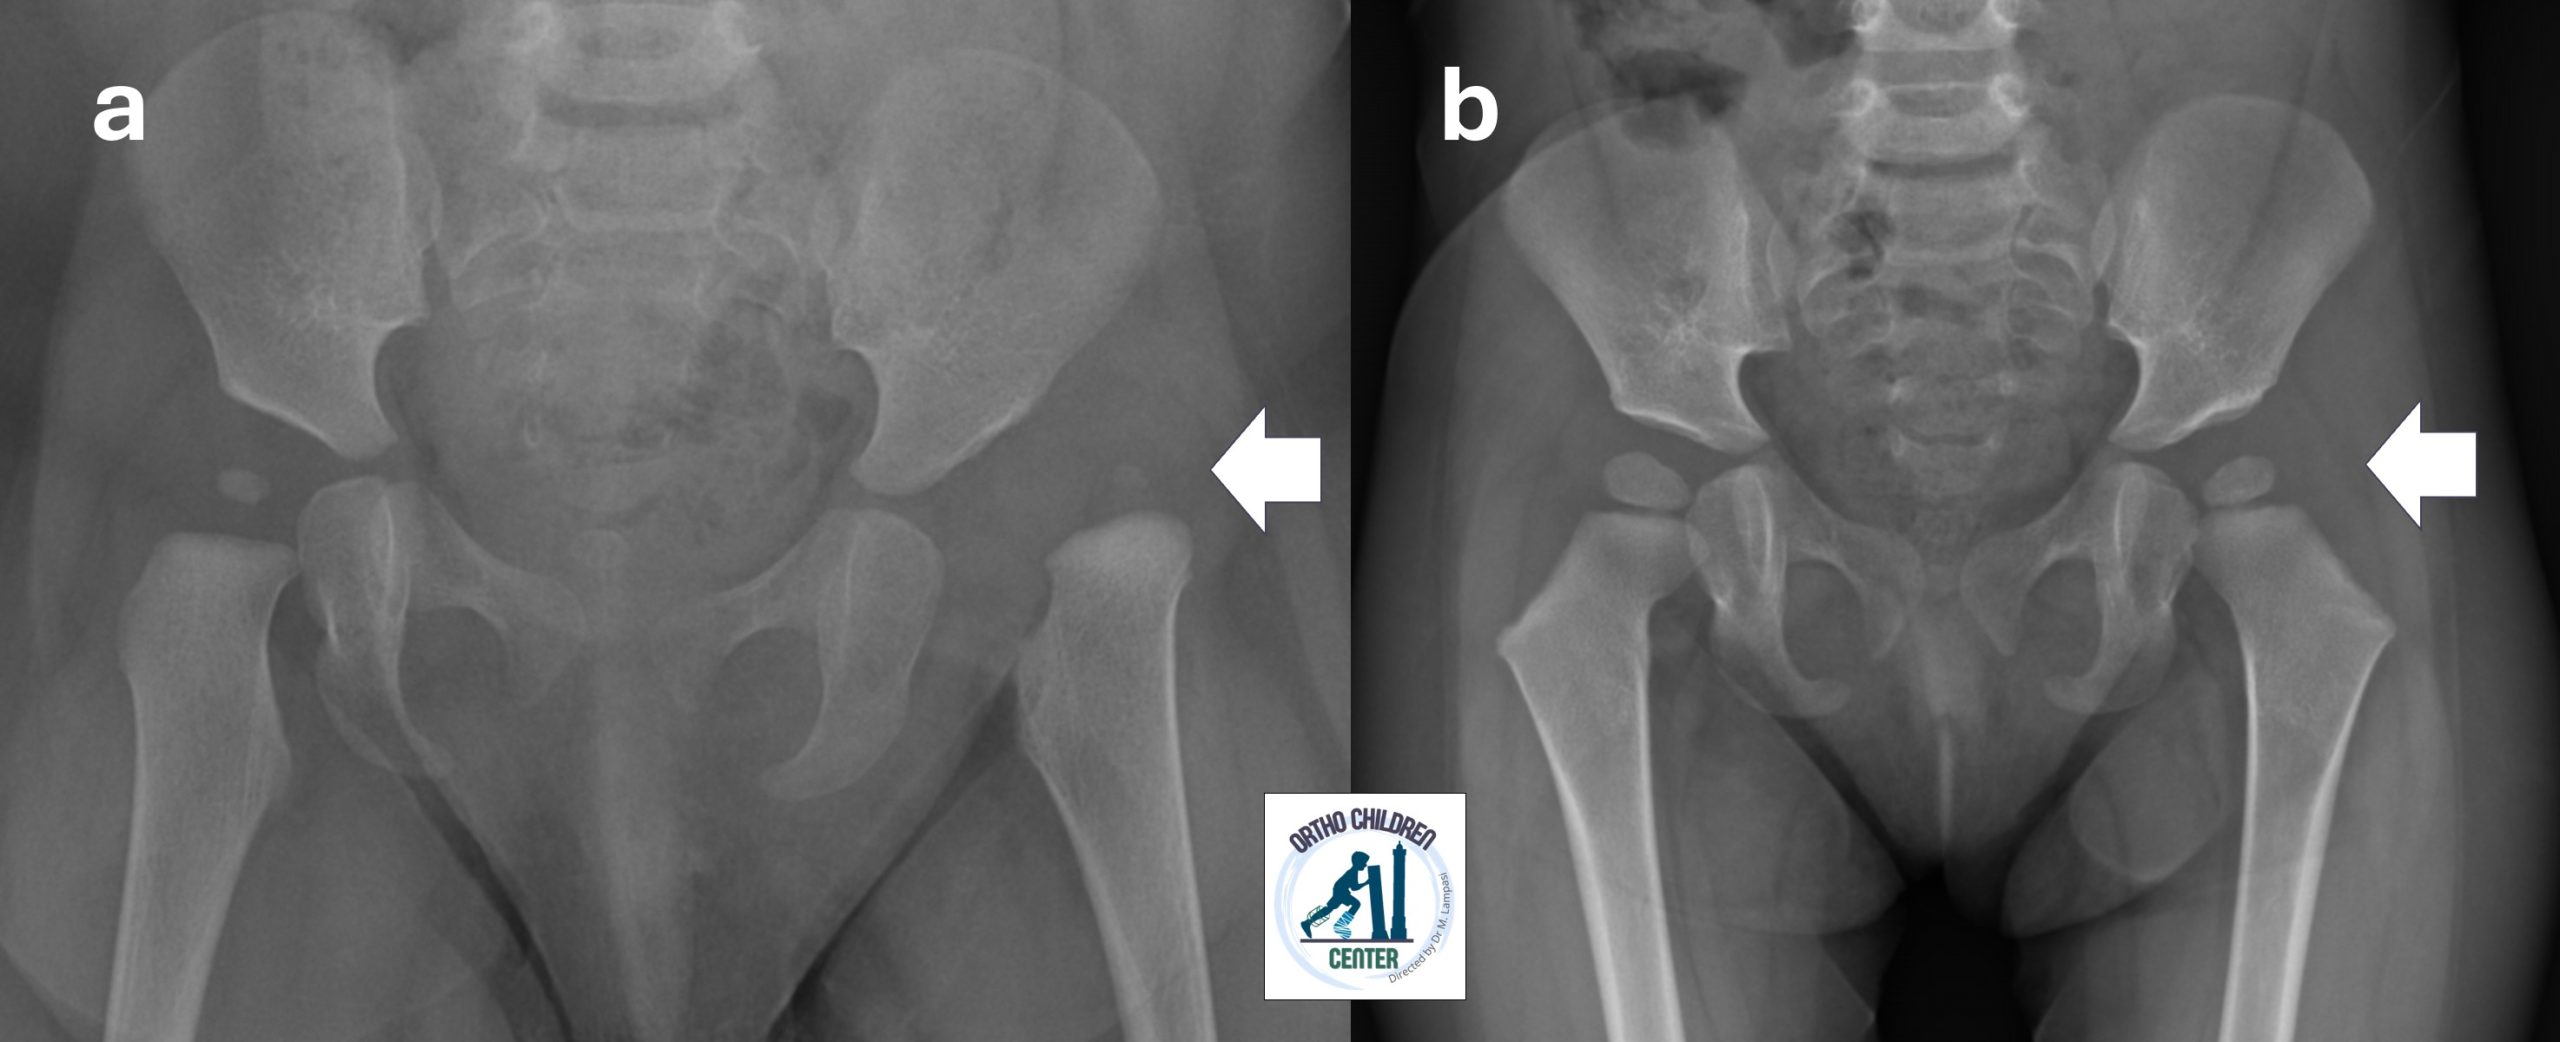

A 9-month-old baby with a late-diagnosed congenital dislocation of the left hip was referred to us from the United Kingdom. Other referral centers had proposed traction (2 weeks), casting (3 months), and procedures under general anesthesia.

Radiographs at 18 months show good centration, without signs of avascular necrosis (AVN).